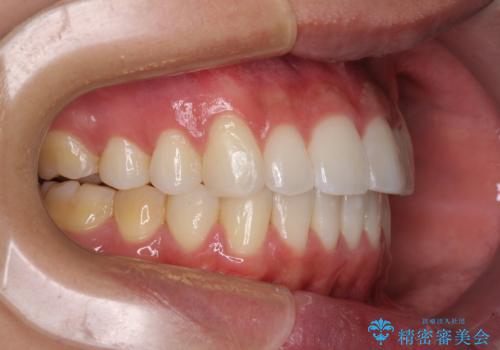

八重歯と奥歯のクロスバイト 上顎骨を拡大してインビザラインで矯正

- 八重歯を気にして来院された患者様です。

八重歯が著しいため、抜歯矯正も視野に入れて検討しましたが、臼歯の咬合関係は正常に近かったので、非抜歯矯正で進める方針としました。

上顎骨の幅が狭く、奥歯がクロスバイトとなっていたため、急速拡大装置を用いて上顎骨を側方拡大し、八重歯を収めるスペースを獲得しつつクロスバイトを改善することとしました。

上顎骨を思い通りに拡大できたため、当初の計画通りに非抜歯矯正で仕上げることができました。